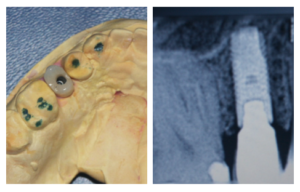

Diente 15 con carga inmediata

Paciente que acude tras fracaso de la pieza 15 para rehabilitación con implante y diente fijo provisional en el día (carga inmediata).

Vista oclusal de la carga inmediata en el modelo y rx apical.